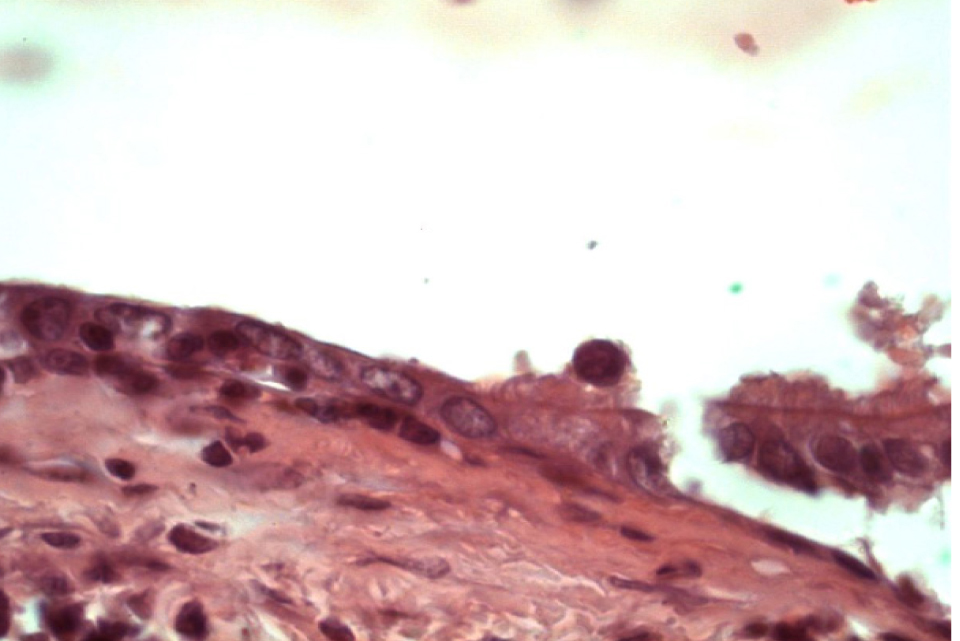

Многорядный мерцательный эпителий бронхов подвергается различным дегенеративным изменениям. Высота эпителиального пласта варьирует. Встречаются участки как плоского, так и кубического эпителия, мерцательные клетки которого содержат немногочисленные реснички (рис. 5).

Рис. 5. Участок различного по высоте эпителия бронха. Окраска гематоксилином и эозином. Ок. 10. Об. 100. Иммерсия